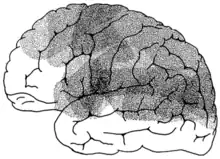

Mixed transcortical aphasia is the least common of the three transcortical aphasias (behind transcortical motor aphasia and transcortical sensory aphasia, respectively). This type of aphasia can also be referred to as "Isolation Aphasia". This type of aphasia is a result of damage that isolates the language areas (Broca's, Wernicke’s, and the arcuate fasciculus) from other brain regions. Broca's, Wernicke's, and the arcuate fasiculus are left intact; however, they are isolated from other brain regions.[2]

In this rare type of aphasia, Broca's area, Wernicke's area, and the arcuate fasciculus are intact but the watershed region around them is damaged.[8] This damage isolates these areas from the rest of the brain. The most frequent etiology of mixed transcortical aphasia is stenosis (narrowing) of the internal carotid artery. Mixed transcortical aphasia can also occur after cerebral hypoxia, cerebral swelling, and any stroke that affects the cerebral artery.[9] Often lesions that cause mixed transcortical aphasia affect both the anterior and posterior perisylvian border zones.[10] Some times the type of aphasia can be determined just by knowing the lesion location.[5] In order for a patient to be diagnosed with mixed transcortical aphasia all other forms of transcortical must be ruled out.[11] Using WAB or the BDAE can rule out global aphasia if the ability to repeat is present.[11] If verbal fluency is depressed transcortical aphasia gets ruled out and if auditory processing and comprehension is weak then it cannot be transcortical motor aphasia.[11]